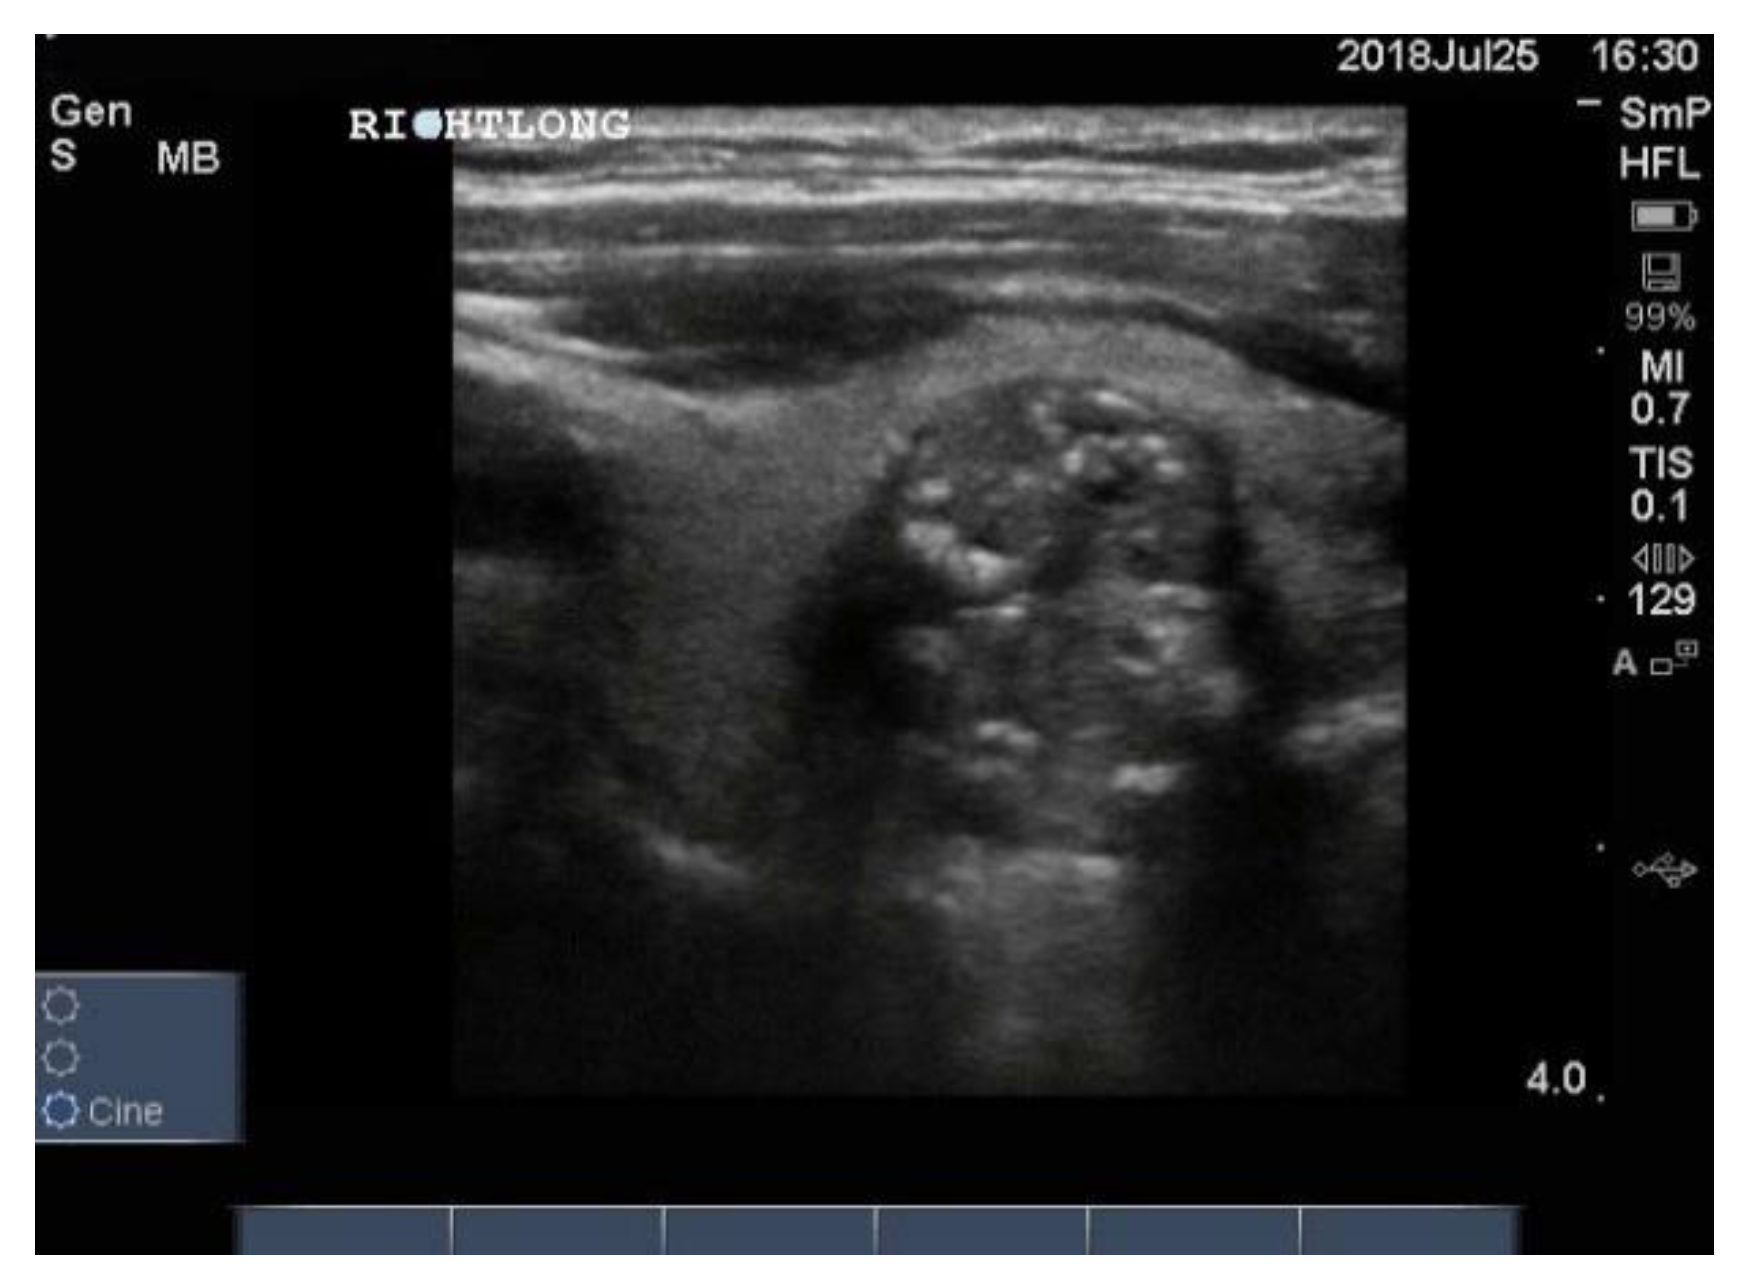

On follow up after treatment, usually total thyroidectomy followed by radioiodine, one looks for abnormal lymph nodes in the neck, indicating local relapse. In the case of papillary carcinoma, involved nodes are round, hypo echoic and may contain microcalcifications (Figure 14). They may have a cystic structure with posterior enhancement. It is recommended that the cervical lymph nodes be examined in all patients who undergo ultrasonography for whatever reason.

Figure 14. Neck ultrasound of enlarged cervical lymph nodes from a patient with papillary thyroid cancer. The enlarged node is oval in shape, very hypoechoic and contains a few of the blotchy microcalcifications typical of papillary cancer. The arrow heads indicate the corners of the node. The little arrow inside referring to an echogenic focus.